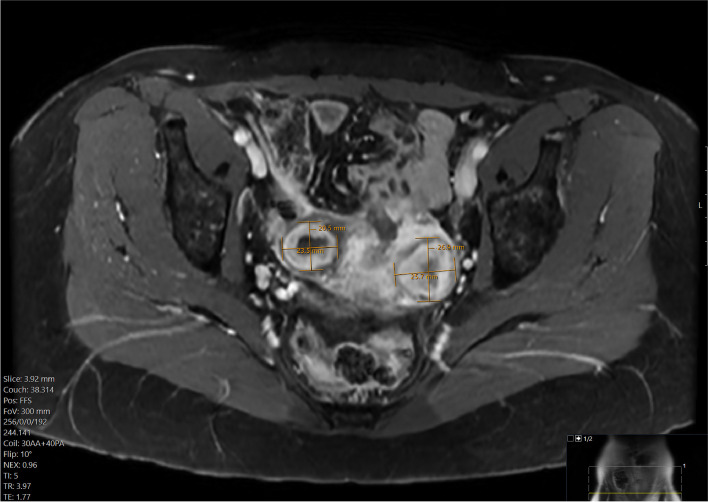

Methods: A 51 year old woman presenting with menorrhagia due to uterine fibroids was referred to interventional radiology for embolization. She was allergic to most opiates and had previously become agitated with IV midazolam, resulting in termination of a previous attempt at embolization. Thus, a combination of three analgesic modalities was used: intraarterial ropivacaine in the uterine arteries, superior hypogastric nerve block with ropivacaine, and intravenous acetaminophen. The patient underwent successful embolization and reported only intermittent pain of 1-2 out of 10 intensity.